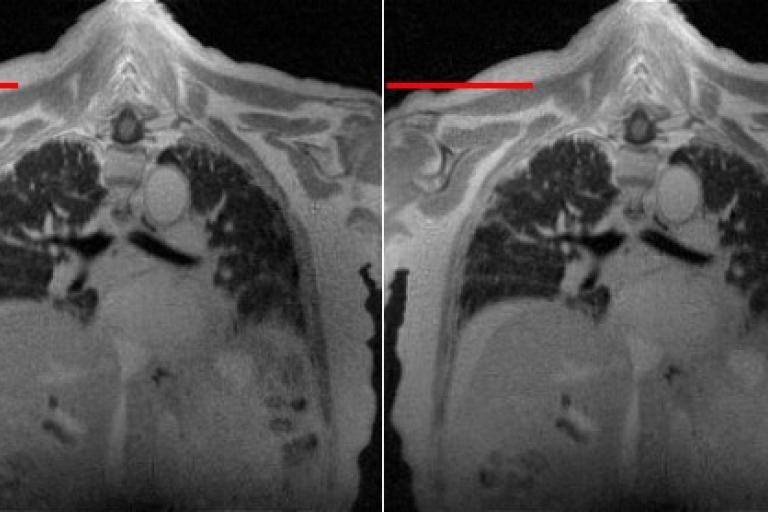

One of the research objects in the lab is on the development of deep-learning algorithms for cardiopulmonary MRI processing, especially the development of unsupervised learning algorithms. We are interested in 2D and 3D cardiopulmonary MRI reconstruction, denoising, super-resolution and segmentation. In this objective, we have developed several algorithms such as G-SToRM, MoCo-SToRM, V-SToRM for real-time cardiopulmonary processing. These work on real-time cardiopulmonary processing wothe best paper award in 2020, and the best paper award finalist in 2021 at IEEE International Symposium on Biomedical Imaging (IEEE ISBI). We've also extended the above algorithms for better performances based on recent advances in deep learning such as the inclusion of Spatial Transformer Networks (STN), Implicit Neural Representations (INR), Graph Convolutional Network (GCN),Kernel method into the algorithms.